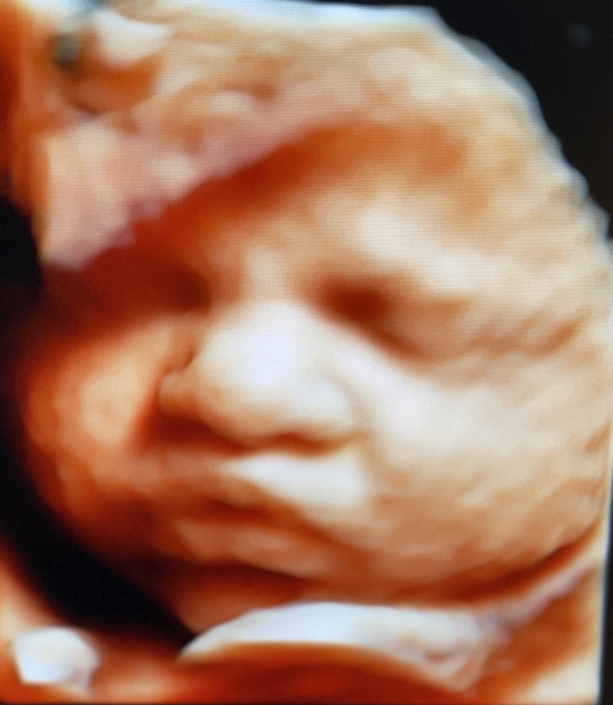

Prenatal Peek®

Prenatal Peek is the leader in 3D 4D Ultrasound. We employ only Certified / Registered Sonographers maintaining unsurpassed standards in 3D ultrasound. You deserve the best! Call us today.